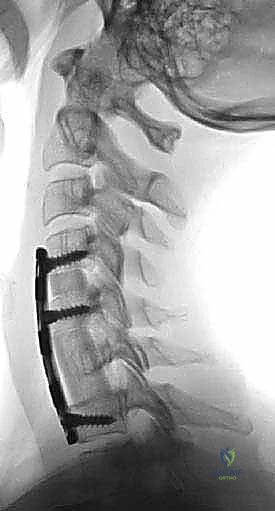

الخطوة 5: التثبيت بالشريحة والمسامير

لضمان ثبات الدعامة ومنع حركتها حتى يكتمل الالتحام العظمي (الذي يستغرق عدة أشهر)، يتم تثبيت شريحة معدنية من التيتانيوم على الجزء الأمامي من الفقرات السليمة (التي تقع أعلى وأسفل الدعامة) باستخدام مسامير طبية خاصة.